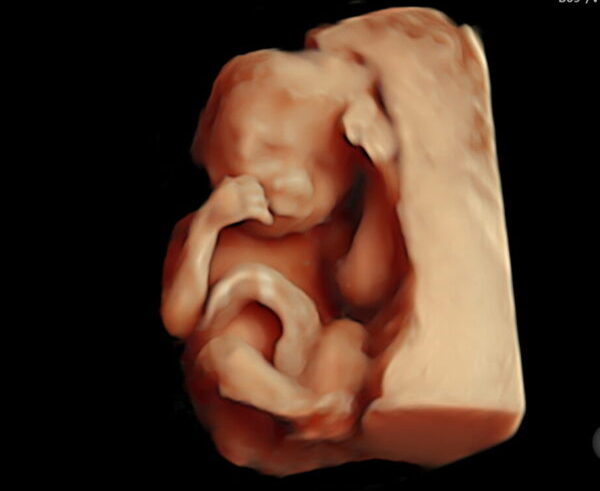

Een 3D/4D HD live echo is alsof je een kijkje neemt in de buik. Bij Baby’s World is het mogelijk om een vroege 3/4D pretecho te maken tussen 13 en 19 weken zwangerschap. Vanaf 20 – 34 weken zwangerschap is het mogelijk om het gezicht van jouw kindje goed in beeld te krijgen met een 3/4D pretecho. De beste periode is tussen de 24 en 30 weken zwangerschap.